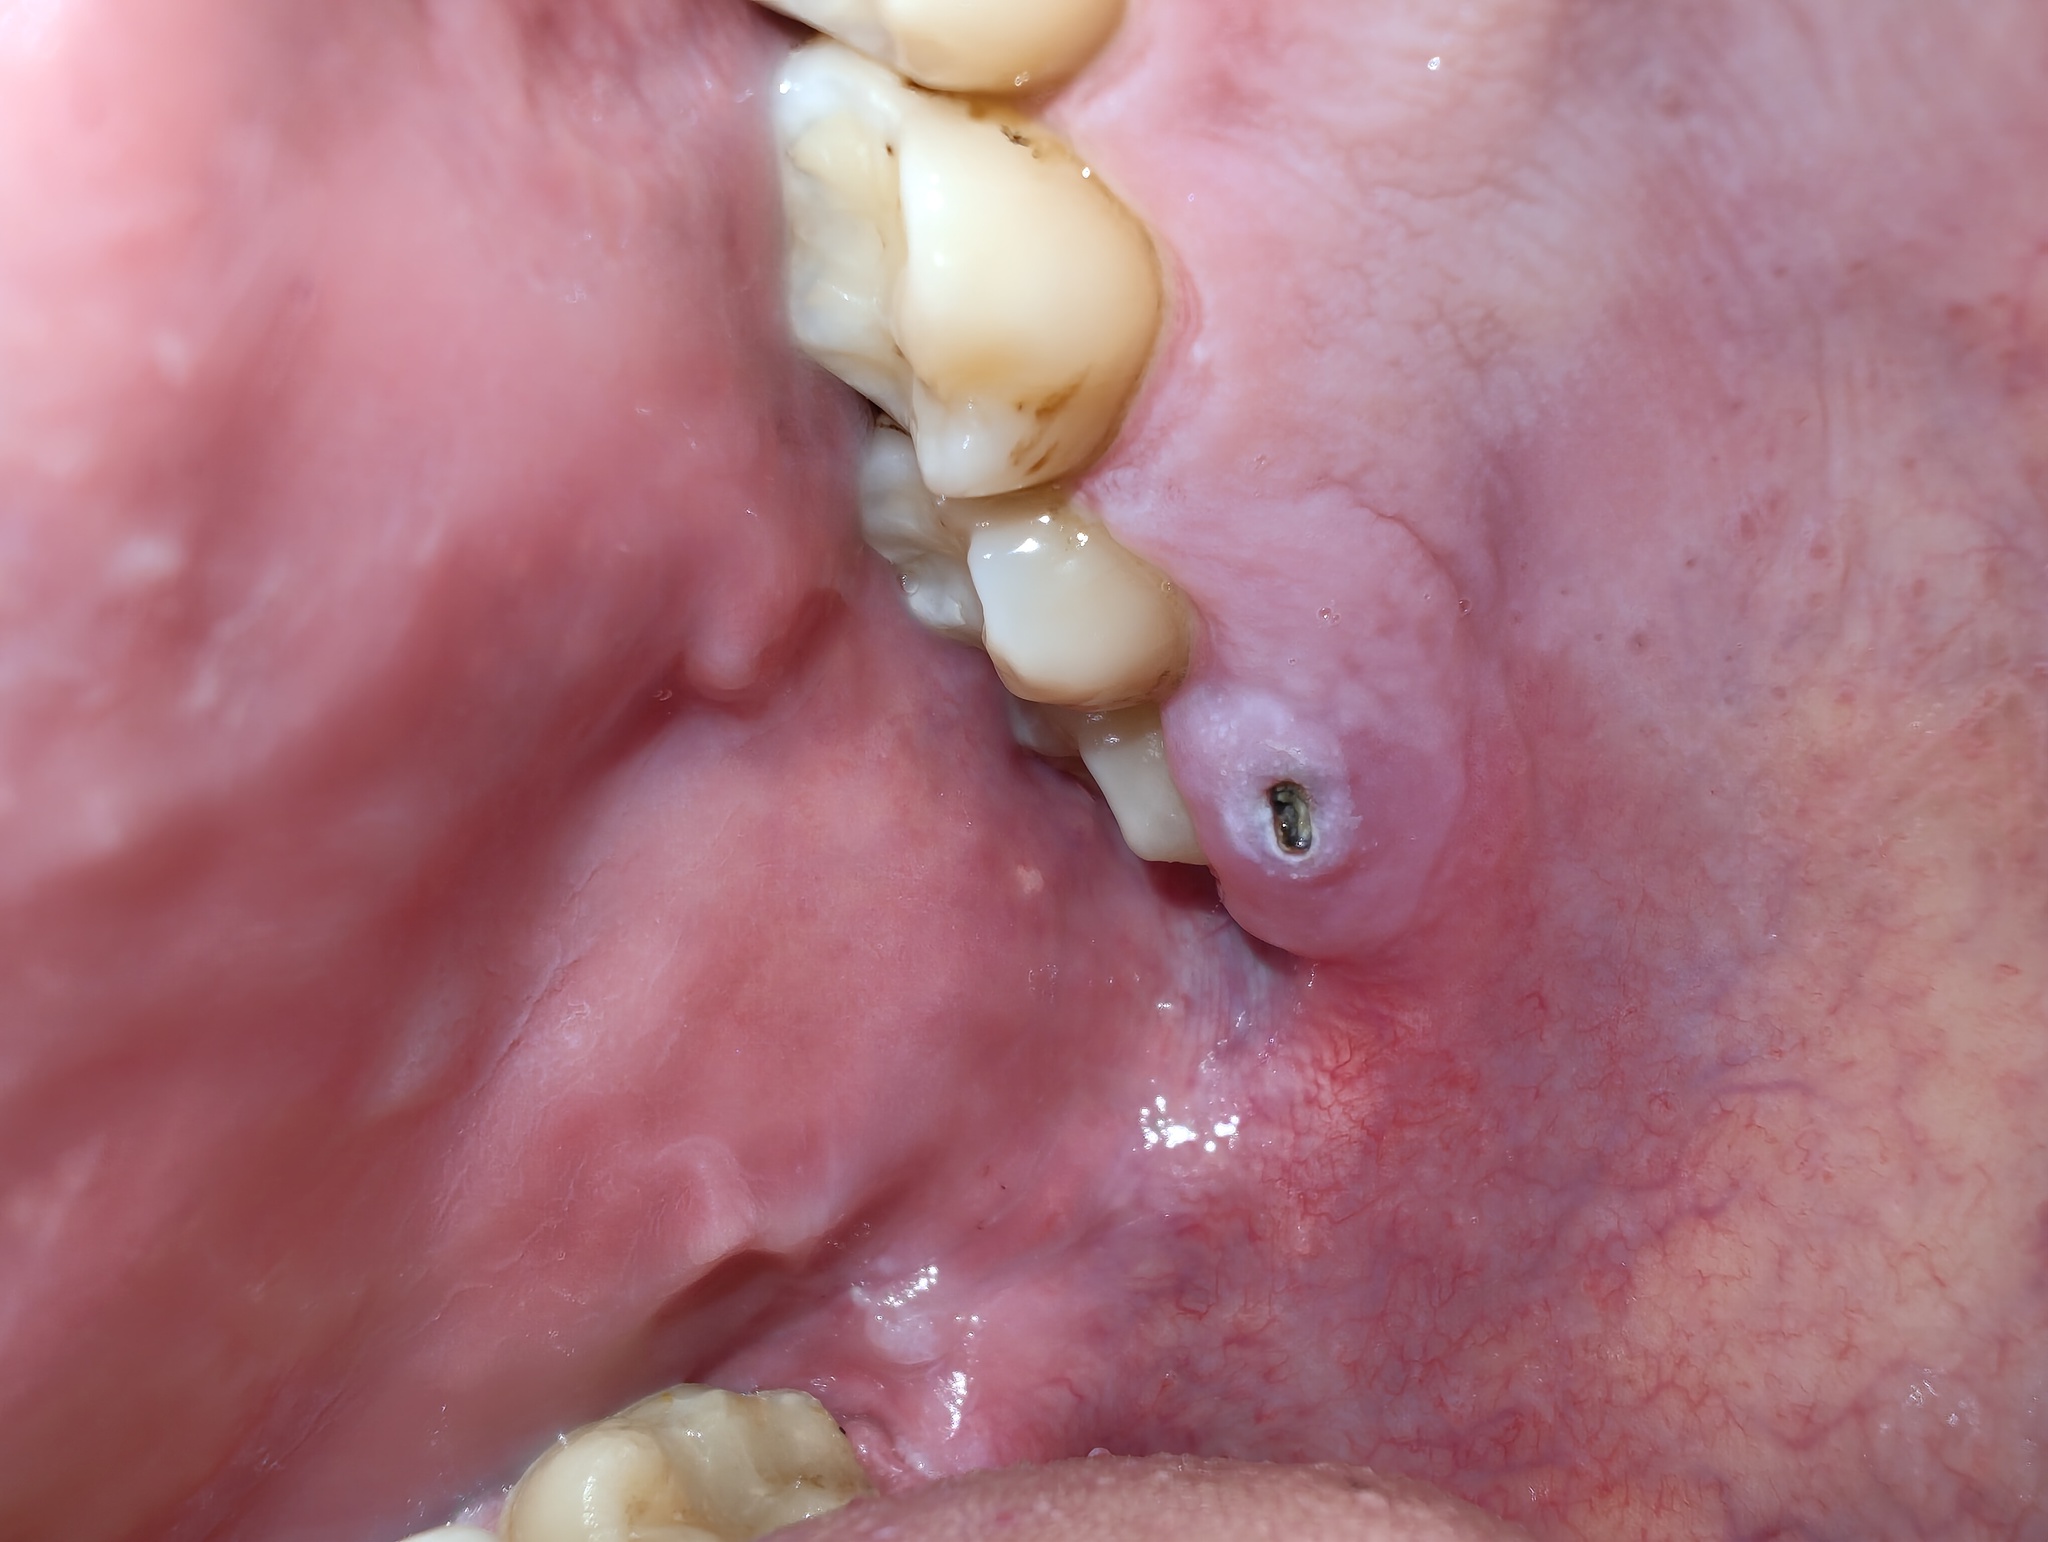

Что это за шняга и к какому врачу идти?

Добрый день, уважаемые пикабушники, сегодня-завтра выходной, больница и стоматология в городе у меня не работают, поэтому прошу знающих сказать, что это у меня вылезло на фото, и к какому врачу идти, и чем хотя бы в выходные это лечить до приема врача, у самого таких знакомых нет.

Впервые такое вижу, немного больно кушать.